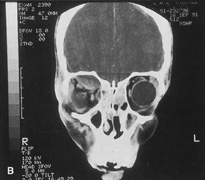

Valuable information about the nature and extent of an orbital pathologic process is provided by imaging studies such as computed tomography (CT) scan, magnetic resonance imaging (MRI), and orbital echography. Better spatial resolution, ready accessibility, and lower cost make CT the preferred choice for orbital imaging in most cases. Orbital fat provides a natural contrast between most adjacent orbital structures on CT scanning, and orbital bones are visualized well. Computed tomography is essential for evaluation of the orbital bones because they cannot be imaged with MRI. Direct coronal or sagittal images are important to identify the relationship of a lesion to the optic nerve so that the surgical approach can be planned to avoid traversing the optic nerve (Fig. 1).

Fig. 1. A. Axial CT scan demonstrating a large, well-encapsulated lesion in the orbital apex. Coronal (B) and sagittal (C) scans demonstrate that the mass lies inferior and medial to the optic nerve within the intraconal space. This information is useful in planning the surgical approach to the mass, which should avoid traversing the optic nerve.